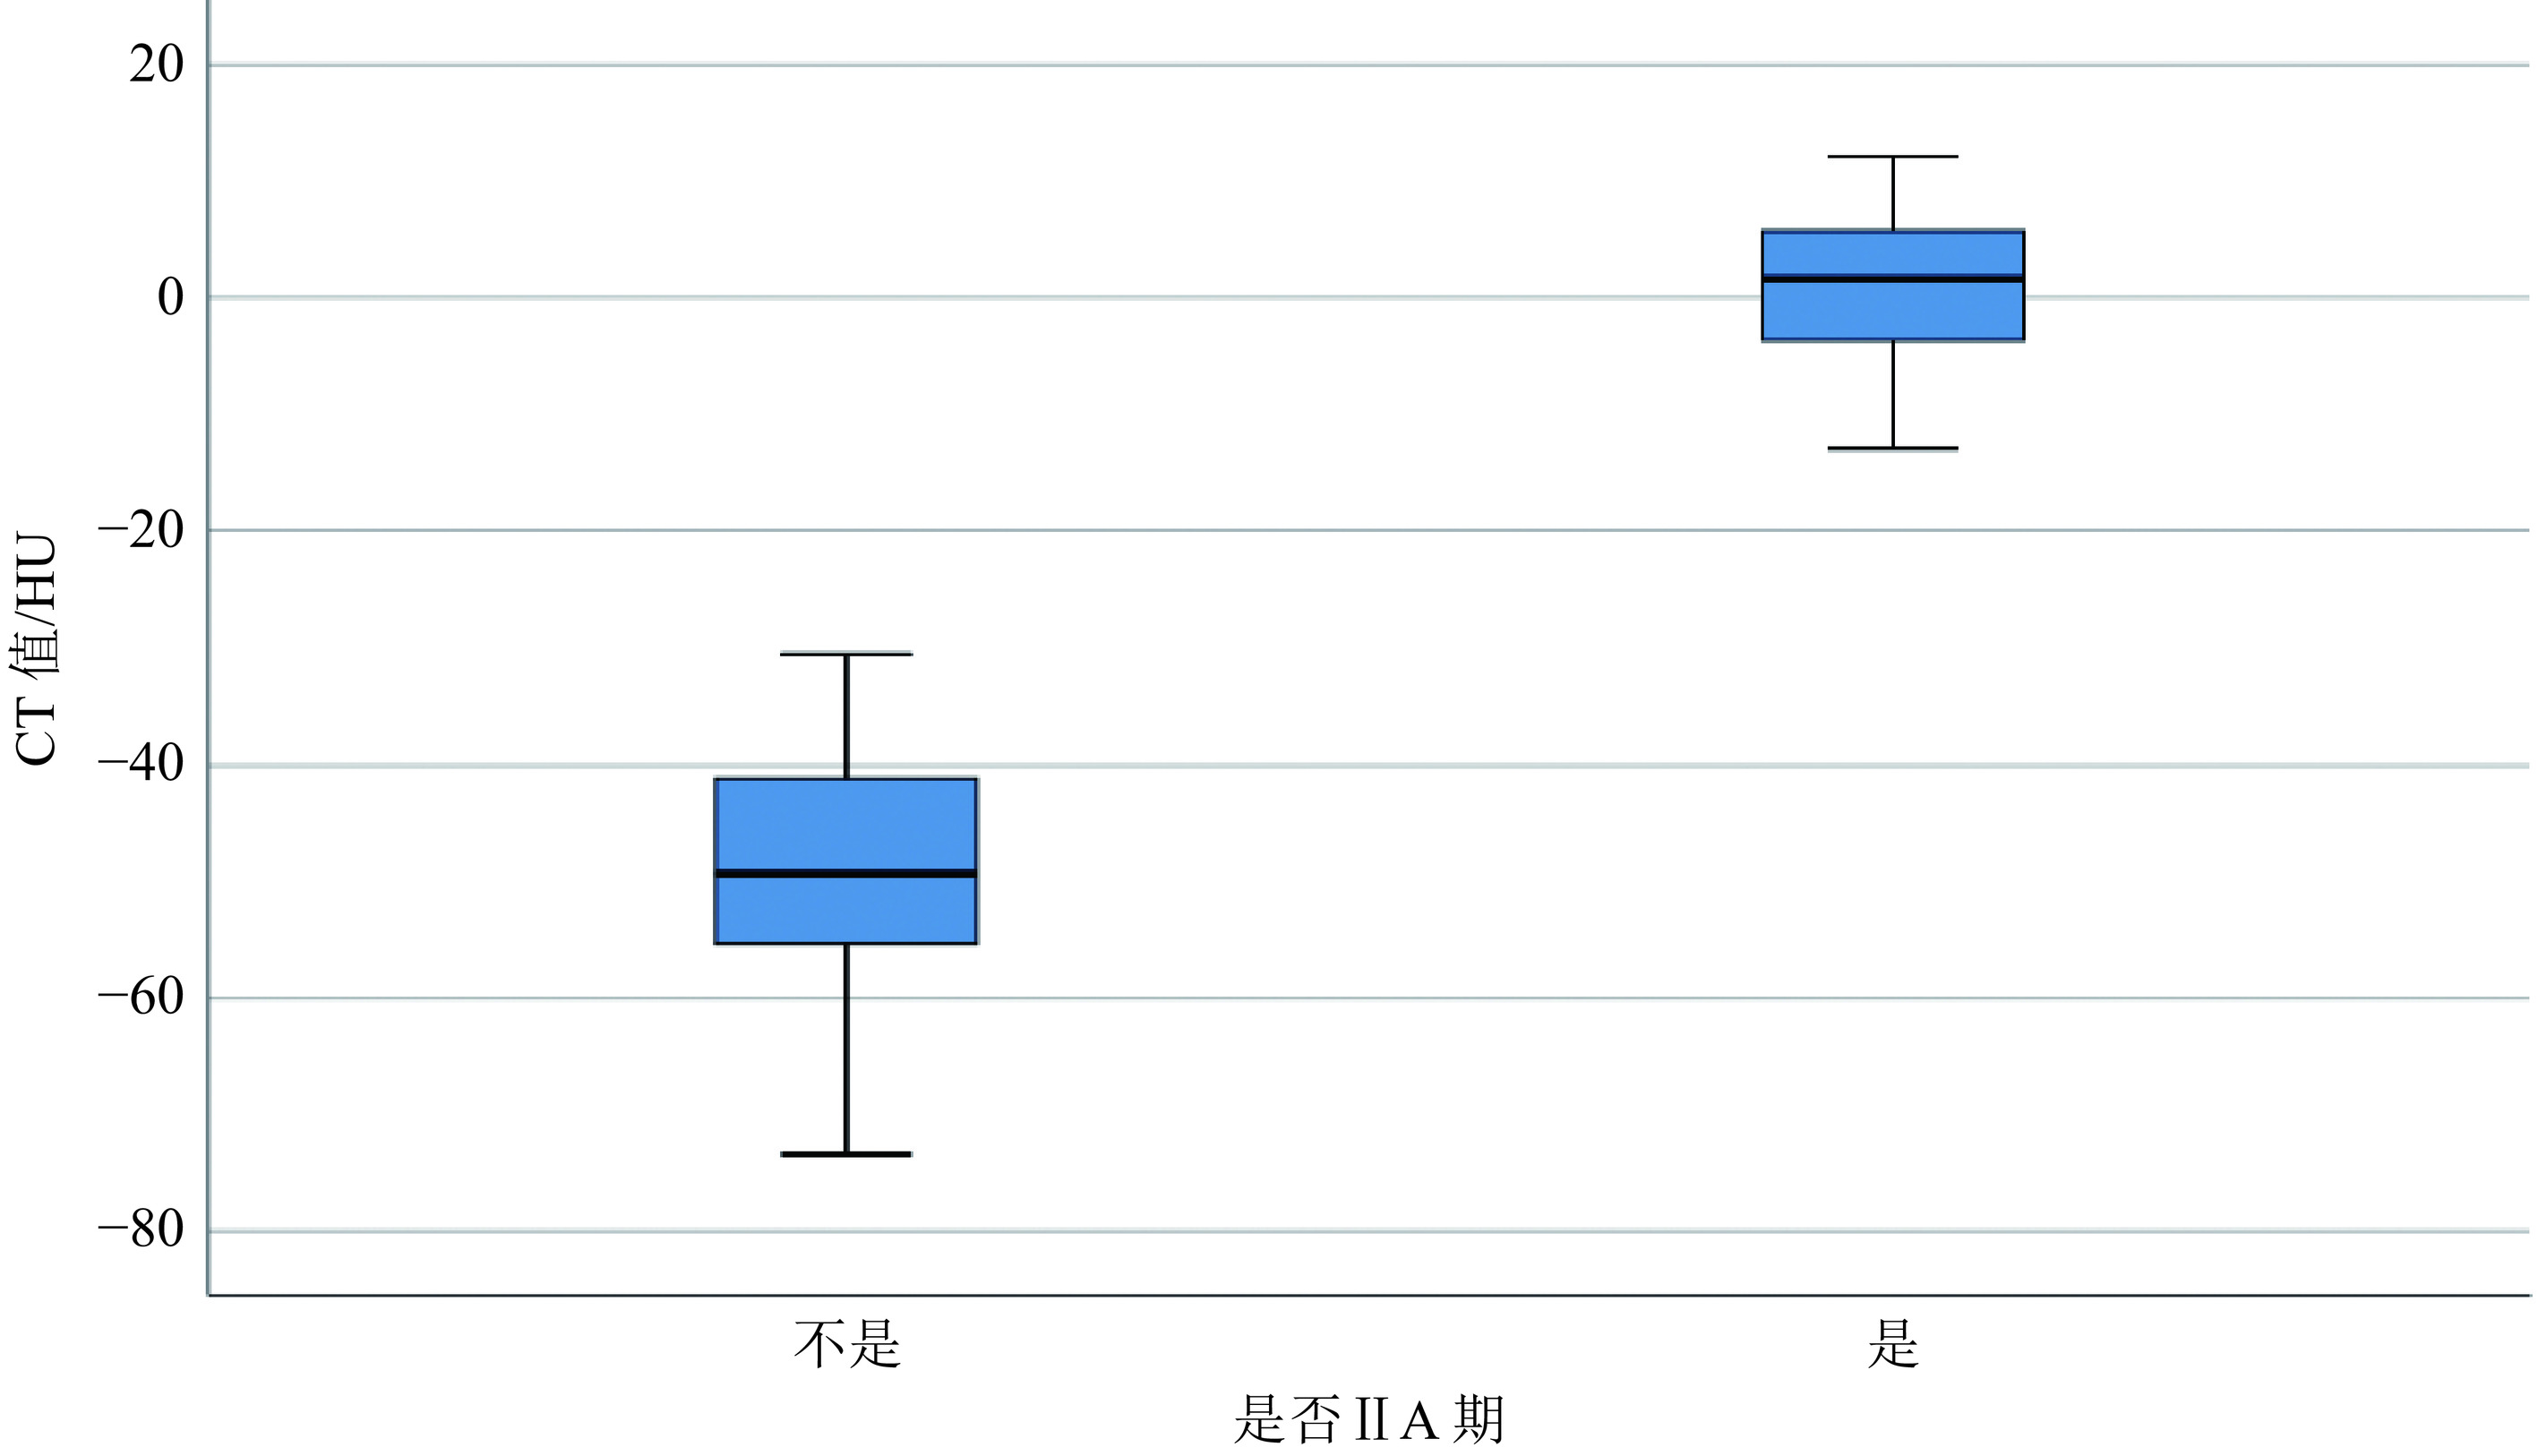

2.2 客观图像分析

以MRI为参考标准,总共有89个ⅡA期区域,D医生在VNCA图像上找出与T2 WI序列上相对应的骨髓水肿区域,测量得出89个异常CT值,对照组(在同一患者的同侧距骨上)测出89个正常骨髓区CT值。总共测出的178个CT值,经SPSS统计软件计算,病变区骨髓CT值(0.55±1.22)HU,对照组骨髓CT值(−48.30±1.24)HU(表3),病变区骨髓CT值与对照组CT值存在统计学差异(P<0.01)(图3)。病变区的CT值ROC曲线显示(图4),AUC值为0.987(95%置信区间:0.974−1.000),病变区骨髓CT值与对照组CT值的最佳截断值为−21.85 HU,此时的敏感性、特异性分别为92%和98.9%。

本研究结果尚显示,OLTⅡA期骨髓异常区与正常骨髓区CT值具有显著统计学差异,前者CT值明显高于后者,最佳截断值为−21.85 HU,其敏感性、特异性分别为92%和98.9%,与Foti等[37]研究结果(截断值为−20 HU,敏感性88%,特异性86.6%)相仿。表明CT定量检测对OLTⅡA期骨髓水肿的诊断具有重要的佐证意义。然而,由于设备、扫描参数、检测位点、受检者年龄等因素影响[38],有研究[37-38]显示最佳截断CT值存在较大差异,需要在实际工作中予以甄别。